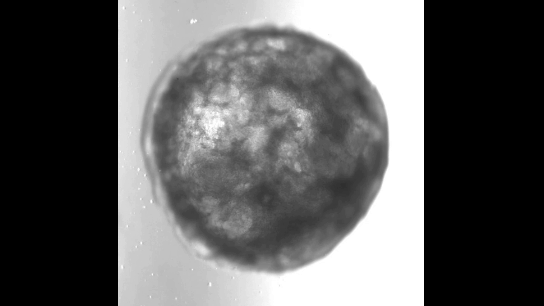

Новая кардиоида спонтанно строилась сама собой без использования матрицы. Учёные, используя шесть сигнальных путей, которые координируют развитие сердца в человеческом эмбрионе, вырастили из пучка стволовых клеток крошечное искусственное «сердце» размером с кунжутное семечко. Более того, этот пульсирующий самоорганизующийся миниатюрный орган имел полую камеру, окружённую стенкой сердечной ткани.

Исследователи заметили, что после всего одной недели роста в лаборатории их масса клеток сформировала трёхмерную структуру, которая ритмично билась, выдавливая жидкость из своей камерной полости.